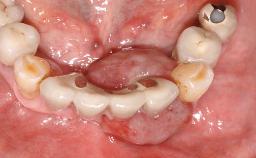

Surgical treatment of a 68-year-old female patient with a distal extension situation in the left mandible. As the CBCT analysis reveals, the bone crest anatomy in the area is not ideal and necessitates an augmentation procedure to achieve a good long-term prognosis for the planned implants and their prostheses.

After the placement of three diameter-reduced two-piece implants the bone is augmented with autologous bone chips and DBBM particles to enlarge the crest volume. The surgery is completed with the application of two membrane layers and primary wound closure.

For soft tissue management, the initial healing caps are replaced with a longer type 8 weeks after implant placement in a second intervention before prosthodontic treatment is initiated.

The case concludes with the presentation of the final prostheses at the 3-year follow-up, demonstrating a stable and pleasing soft- and hard-tissue situation.